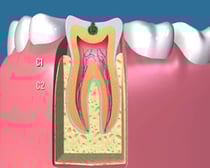

健全歯:

何も虫歯のない、健康な歯の状態です。

C1:

歯の表面に穴が少し開いて、表層のエナメル質に限局して虫歯に犯されている状態です。まだ症状が全く出ない状態です。レジン治療が適応となります。

C2:

歯の深部にある象牙質まで達した虫歯です。なかなか症状に出てくることが少ないですが、この状態が大きくなると甘いものや冷たいもので歯がしみたり、歯の間に食べカスが詰まりやすくなります。比較的小さい場合はレジン充填の適応となりますが、むし歯が大きくなるとインレー修復などになってしまいます。